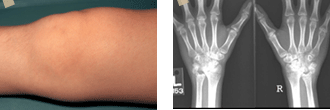

어른의 경우와 마찬가지로 관절에 통증이 있고, 관절이 부으면서 열이 나고 관절을 움직이기가 불편한 증상들이 발생합니다. 그러나 어른의 경우와 달리 크게 통증을 호소하는 경우가 드뭅니다. 따라서 관절염이 생기고도 몇 달 동안 발생한 사실을 부모님들이 알아차리지 못하는 경우가 생기기도 합니다.

관절통과 같은 증상 이외에 형태에 따라 심한 고열과 붓기도 하고, 눈에 충혈이 생기기도 합니다.

그러나 대체로 16세이하의 어린이에서 6주내지 3개월이상 지속되는 관절염이 있으면서 다른 관절염이 배제될 때, 소아기 특발성 관절염이라고 진단할 수 있습니다.

소아기 특발성 관절염은 발생하는 양상에 따라 3가지 형태로 흔히 구분하게 됩니다.

즉 전신형, 다발성 관절형, 그리고 소수관절형으로 나눌 수 있습니다.